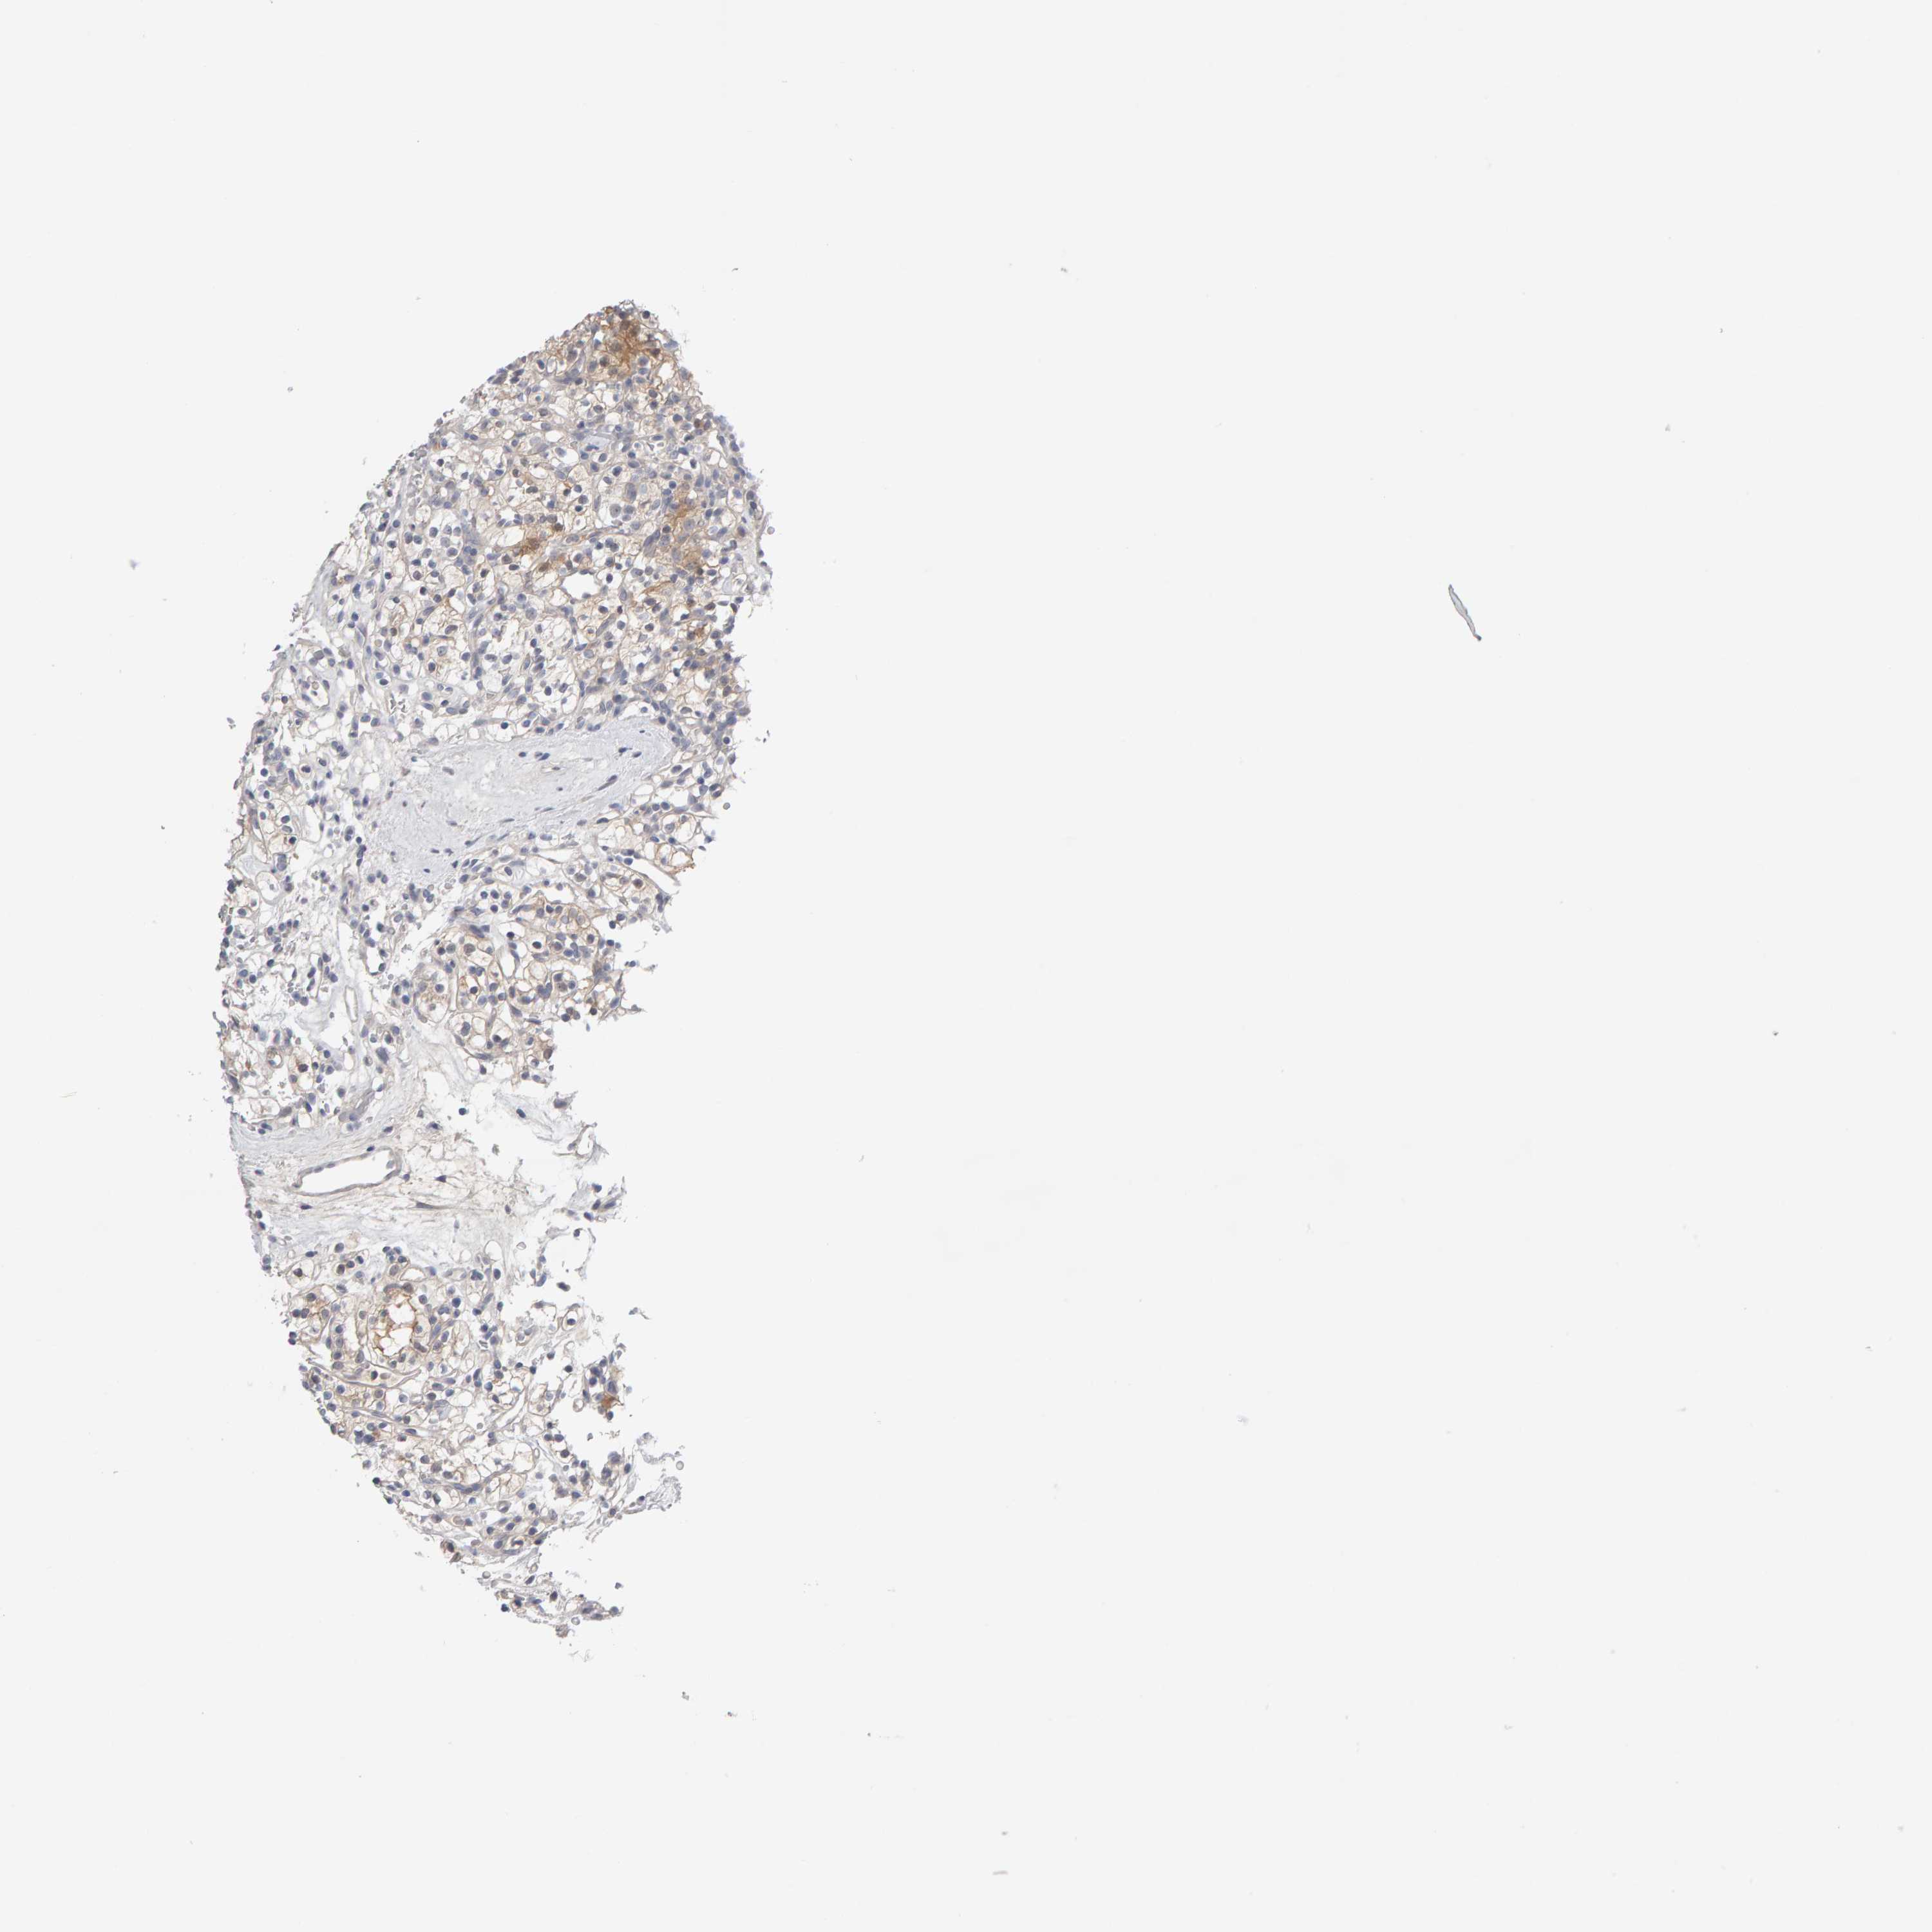

KIDNEY RENAL PAPILLARY CELL CARCINOMA (TCGA) - Interactive survival scatter ploti

The Survival Scatter plot shows the clinical status (i.e. dead or alive) for all individuals in the patient cohort, based on the same data that underlies the corresponding Kaplan-Meier plots. Patients that are alive at last time for follow-up are shown in blue and patients who have died during the study are shown in red.

The x-axis shows the expression levels (FPKM) of the investigated gene in the tumor tissue at the time of diagnosis. The y-axis shows the follow-up time after diagnosis (years). Both axes are complimented with kernel density curves demonstrating the data density over the axes. The top density plot shows the expression levels (FPKM) distribution among dead (red) and alive patients (blue). The right density plot shows the data density of the survived years of dead patients with high and low expression levels respectively, stratified using the cutoff indicated by the vertical dashed line through the Survival Scatter plot. This cutoff is automatically defined based on the FPKM cutoff that minimizes the p-score. The cutoff can be changed by dragging the vertical line or by entering a cutoff value in the square labeled "Current cut-off".

Under the Survival Scatter plot the p-score landscape (black curve; left axis) is shown together with dead median separation (red curve; right axis). Dead median separation is the difference in median mRNA expression between patients who have died with high and low expression, respectively. It is calculated as follows: median FPKM expression of dead patients with high expression - median FPKM expression of dead patients with low expression. This is intended to aid the user in visually exploring custom cutoffs and the associated p-scores and dead median separation.

Individual patient data is displayed and can be filtered by clicking on one or more of the category buttons on the top of the page. Categories describing expression level and patient information include: high, low, alive, dead, female, male and tumor stages. The scale of the x-axis can be toggled between linear and log-scale by clicking on the "x log" button. Mouse-over function shows TCGA ID, patient information and mRNA expression (FPKM) for each patient.

& Survival analysisi

Kaplan-Meier plots summarize results from analysis of correlation between mRNA expression level and patient survival. Patients were divided based on level of expression into one of the two groups "low" (under cut off) or "high" (over cut off). X-axis shows time for survival (years) and y-axis shows the probability of survival, where 1.0 corresponds to 100 percent.

GFUS is not prognostic in Kidney Renal Papillary Cell Carcinoma (TCGA)